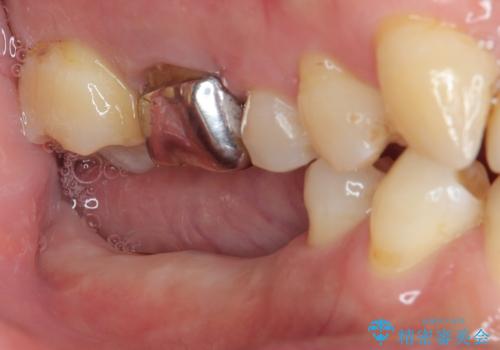

- 以前抜歯をして歯がないところにインプラント治療をしたいと来院された患者様です。

1年くらい前に他院で抜歯をしたそうです。

レントゲンで確認すると骨は十分にあるので通法通りインプラントによる補綴治療を行いました。